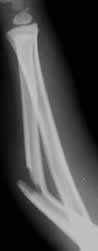

Rx lateral. Fractura angulada anteriormente, en la diáfisis del cúbito.

Fig 45. Angulación posterior.

A: Rx lateral. Fractura del radio distal con desplazamiento posterior del extremo distal.

B: Rx lateral. Fracturas del brazo, con leve angulación posterior del radio.